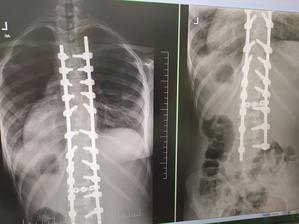

A na akú odchýlku sa jej po operácii podarilo dostať? Mala viac ako 60 stupňov a teraz?

6 a 8 stupňov